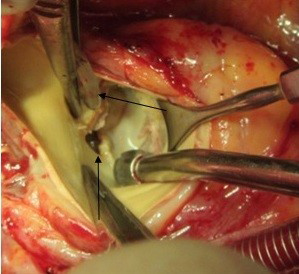

A 37-year-old female patient was referred to our hospital following a full course of Brucella endocarditis in a general hospital for emergency surgery of Brucella endocarditis of aortic and mitral valve. The patient’s past medical history revealed living in endemic area of Brucella infection and a history of consumption of unpasteurized milk products. Her medical history was unremarkable except for sacroiliac arthritis. She had been admitted in a general hospital for assessing fever over the last month. After detecting a positive blood culture for Brucella without its bio-typing, she was treated by following triple combination of drugs consisting of oral rifampin 900 mg per day (qd), oral doxycycline 100 mg twice per day (bid) and gentamicin 80 mg intravenously three times per a day (tid) adjusted with blood levels of drugs and serum BUN and creatinine level. Upon admission, the patient was feverous, tachycardic, her blood pressure was low (80/20), and she had dyspnea. On neurologic examination, the patient was awake and oriented; her skin was cold and damp. The patient’s previous blood cultures at three different times showed a Brucella infection. White blood cell count: 12,000/mm–3 with 70% neutrophils, platelet count: 80,000/mm–3, hemoglobin: 9 g/dl, C-reactive protein: 60 mg/dl, erythrocyte sedimentation rate: 75 mm/h, blood urea nitrogen (BUN): 60 mg/dL, and creatine (Cr): 3.9 mg/dL. Urinalysis revealed no hematuria and 24-hour (diurnal) urinalysis (UA) revealed proteinuria. Serum agglutination tests were positive (titer>1:1,500), and enzyme-linked immunosorbent assay tests for anti-Brucella IgG and IgM antibodies were strongly positive (150 U/ml and 52 U/mL, respectively). A transthoracic echocardiogram (TTE) delineated destruction of mitral and aortic valves by multiple vegetation and multiple small and large aortic ring abscesses extended to surrounding tissue and perforated to right atrium, main pulmonary artery and formation a pocket over the left atrial roof (Figure 1 [Fig. 1], Figure 2 [Fig. 2]). The ejection fraction (EF) was 50% and pulmonary pressure was 60 mmHg. There was severe aortic, mitral and tricuspid valve regurgitation. The patient continued to use the previous anti-Brucella drugs orally while additional evaluations were performed. Due to the patient’s congestive heart failure (CHF) in addition to her multiple mobile aortic and mitral valve vegetation, it was decided that aortic and mitral valve replacement shall be performed immediately. The patient was scheduled for an emergency double valves procedure. However, the night before the surgery, she was intubated due to respiratory distress and was subsequently connected to mechanical ventilator. The patient suffered from severe pulmonary edema caused by CHF that required mechanical ventilation. After intubation, the patient became hypotensive and oliguric needing inotropic drugs use. The patient’s hemodynamic became stabilized and she was taken to the operating room. The intra-operative transesophageal echocardiogram (TEE) did not reveal any new findings. The patient was taken to operating room and a median sternotomy was performed and aortic and bi-cava cannulation was done. After opening the pericardium, it was found that the aortic root was severely attached to the surrounding tissue by inflammatory reaction caused by perforation of abscess in left coronary sinus to roof of left atrium as observed in TEE. The ascending aorta was cross-clamped, and after transverse transaction of the ascending aorta, cardioplegin was indirectly infused to coronaries ostium to induce cardiac arrest. After moderate hypothermic cardioplegic arrest, the umbilical tape was put around both the superior vena and inferior vena cavae and they were snared. The right atrium and left atrium were opened superior and inferior to the atrioventricular groove. Further, intra-operative inspection of right atrium showed small vegetations in crater of fistula entrance to right atrium in antero-medial region of tricuspid ring (Figure 3 [Fig. 3]). However, the tricuspid valve was not involved in infective endocarditis. Intra-aortic root inspection revealed a defect in non-aortic coronary sinus filled with necrotic materials and an abscess that perforated through the area above the tricuspid valve (Figure 4 [Fig. 4]). There was also a fistula between the left-coronary sinus, just near the left coronary ostium to the main pulmonary artery (Figure 5 [Fig. 5]). Further intra-operative perception of aortic root revealed a pocket filled by abscess through a defect in left coronary sinus just located over the roof of the left atrium (Figure 6 [Fig. 6]). In addition to the aforementioned fistulas, multiple vegetations were observed on both mitral and aortic valves that caused severe destruction of both valves causing grave regurgitation (Figure 7 [Fig. 7]). It apeared that mitral valve vegetations were caused by regurgitated aortic valve flow that impinged on aorto-mitral fibrous continuity and subsequently caused the penetration and destruction of the native mitral valve (Figure 8 [Fig. 8]). This infective tissue involved the valve. The abscess was completely debrided to restore and find underlying normal tissue. After debridement of the perforation’s site of the left coronary sinus and cleaning of the performed pocket over the left atrial roof, the aortic defect was repaired by fresh autologous pericardium patch that was used in the external side of the ascending aorta. The fistula tract to main pulmonary artery was closed from intra-pulmonary side of fistula by 4/0 proline sutures, as the closure of small fistula to right atrium. After closing of all three fistula and reconstructing the left sinus of valsalva and replacement of both valves, an oval-shaped fresh pericardial patch was utilized in a sino-tubular junction positioned just close to the superior vena cava, which helped in a tension-free approximation of aortotomy incision. Because the perforation of abscess along the conduction system caused bundle branch block and disturbances of other conduction branches, the atrial and ventricular epicardial pacing wires were used for sequential atro-ventricular pacing. The patient was admitted to the surgical intensive care unit for further control and treatment. Weaning from mechanical ventilation was complicated with tachypnea and grave respiratory distress. Extubation was delayed on the 9th post-operative day after performing a tracheostomy for the better cleaning of respiratory tract secretion and facilitation of extubation. Transient renal and hepatic failure also complicated the postoperative course of surgery. The serum blood nitrogen and creatinine raised to 90 and 5.5 subsequently and was managed accordingly by three times of peritoneal dialysis. Her hepatic and kidney dysfunction recovered relatively in 15th day of operation. A TEE in discharge time revealed a normal functioning of both bioprosthetic valves; however, a mild paravalvular leakage was observed in aortic position. Moreover, correction of all fistulas was successful and no residual flow signal in area of fistula repair was found. She was discharged home on the 25th day after admission.

Figure 7: Fistula to pulmonary artery (black arrow)

Figure 8: Left coronary defect imposing as a fistula to the left atrial roof (vertical arrow); cardioplegia catheter positioned at the left osmium (horizontal arrow)